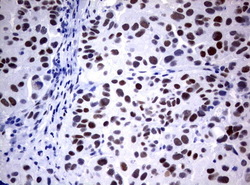

- Main image

- Experimental details

- Immunohistochemical staining of paraffin-embedded Human prostate tissue using anti-FOXP1 mouse monoclonal antibody. (UM800020; heat-induced epitope retrieval by 1 mM EDTA in 10mM Tris, pH8.0, 120C for 3min)

- Validation comment

- IHC